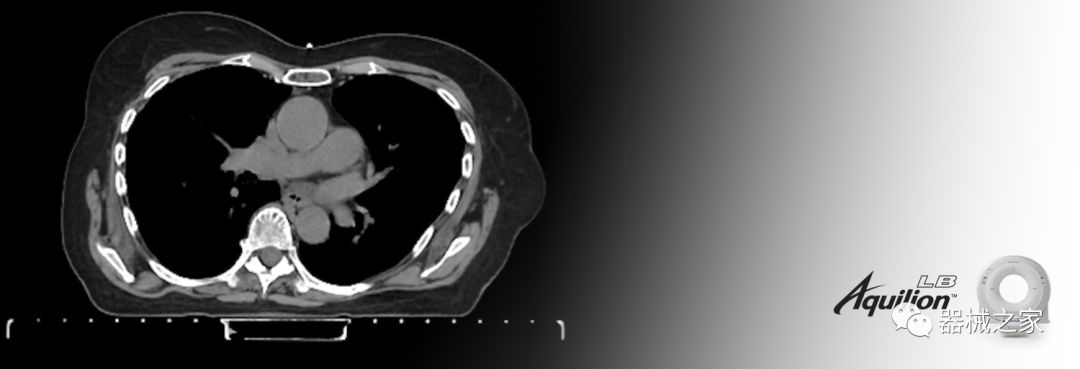

在以患者為中心的放射腫瘤學(xué)領(lǐng)域,計(jì)算機(jī)斷層掃描(CT)的可訪問(wèn)性,可重復(fù)性和靈活性至關(guān)重要。為了建立這些價(jià)值,佳能醫(yī)療系統(tǒng)美國(guó)公司現(xiàn)在正在擴(kuò)大其放射腫瘤學(xué)CT模擬產(chǎn)品,包括Aquilion Prime SP和Aquilion Lightning 80高級(jí)CT系統(tǒng)。除了Aquilion LB之外,Aquilion Prime SP和Aquilion Lightning 80現(xiàn)在還包括放射治療(RT)選項(xiàng),可為腫瘤學(xué)規(guī)劃提供高質(zhì)量的CT成像和精密工具。

擴(kuò)展視野(EFOV)可以看到更多的解剖結(jié)構(gòu)。Aquilion LB采用85 cm EFOV,而Aquilion Prime SP和Aquilion Lightning 70采用70 cm EFOV。

兩個(gè)CT系統(tǒng)均采用0.5 mm x 80排PUREViSION探測(cè)器技術(shù)(可配置并從80-160現(xiàn)場(chǎng)升級(jí)),78 cm孔徑,50 cm視野,AIDR(自適應(yīng)迭代劑量減少)3-D和SEMAR(單個(gè))能量金屬神器減少)技術(shù)。

Aquilion LB專為滿足腫瘤學(xué)挑戰(zhàn)而設(shè)計(jì),同時(shí)優(yōu)先考慮患者護(hù)理。Aquilion LB的內(nèi)徑為90 cm,能夠幫助復(fù)雜的患者設(shè)置并提高患者的舒適度。CT模擬定位可以輕松鏡像放射治療定位,更加自信。該系統(tǒng)采用0.5 mm x 16排(32層)PUREViSION探測(cè)器技術(shù),70 cm視野,AIDR 3D和SEMAR技術(shù)。